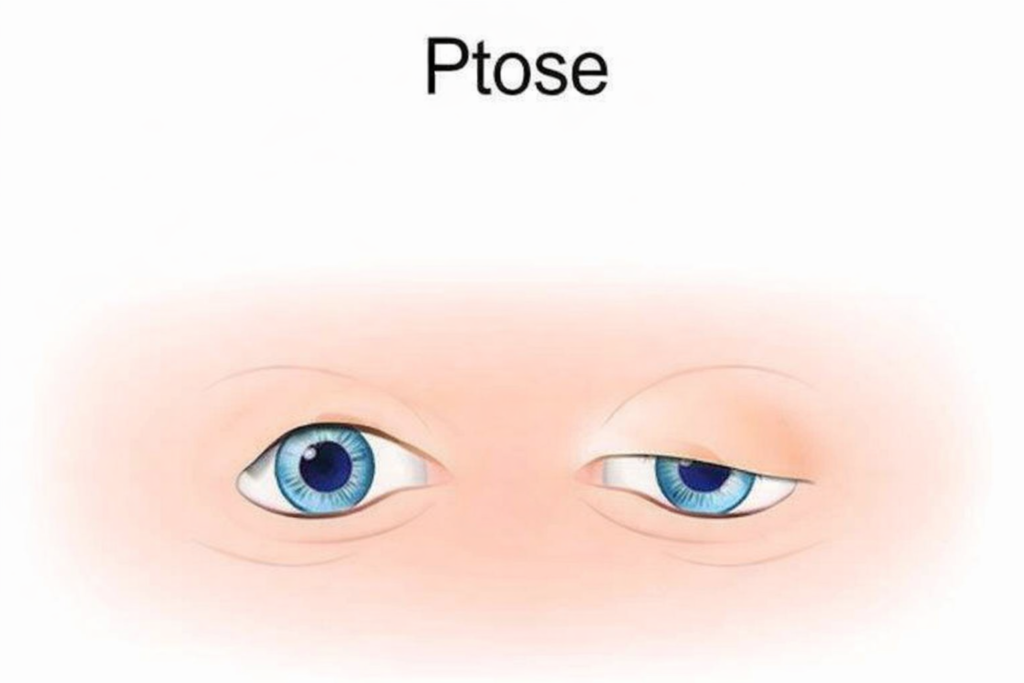

Quando o aneurisma cresce, ele pode pressionar partes do cérebro e causar alguns sintomas, como:

- Queda de pálpebra (Ptose palpebral)

Em situações mais raras, quando o aneurisma cresce lentamente, ele pode causar sinais como:

- Pálpebra caída